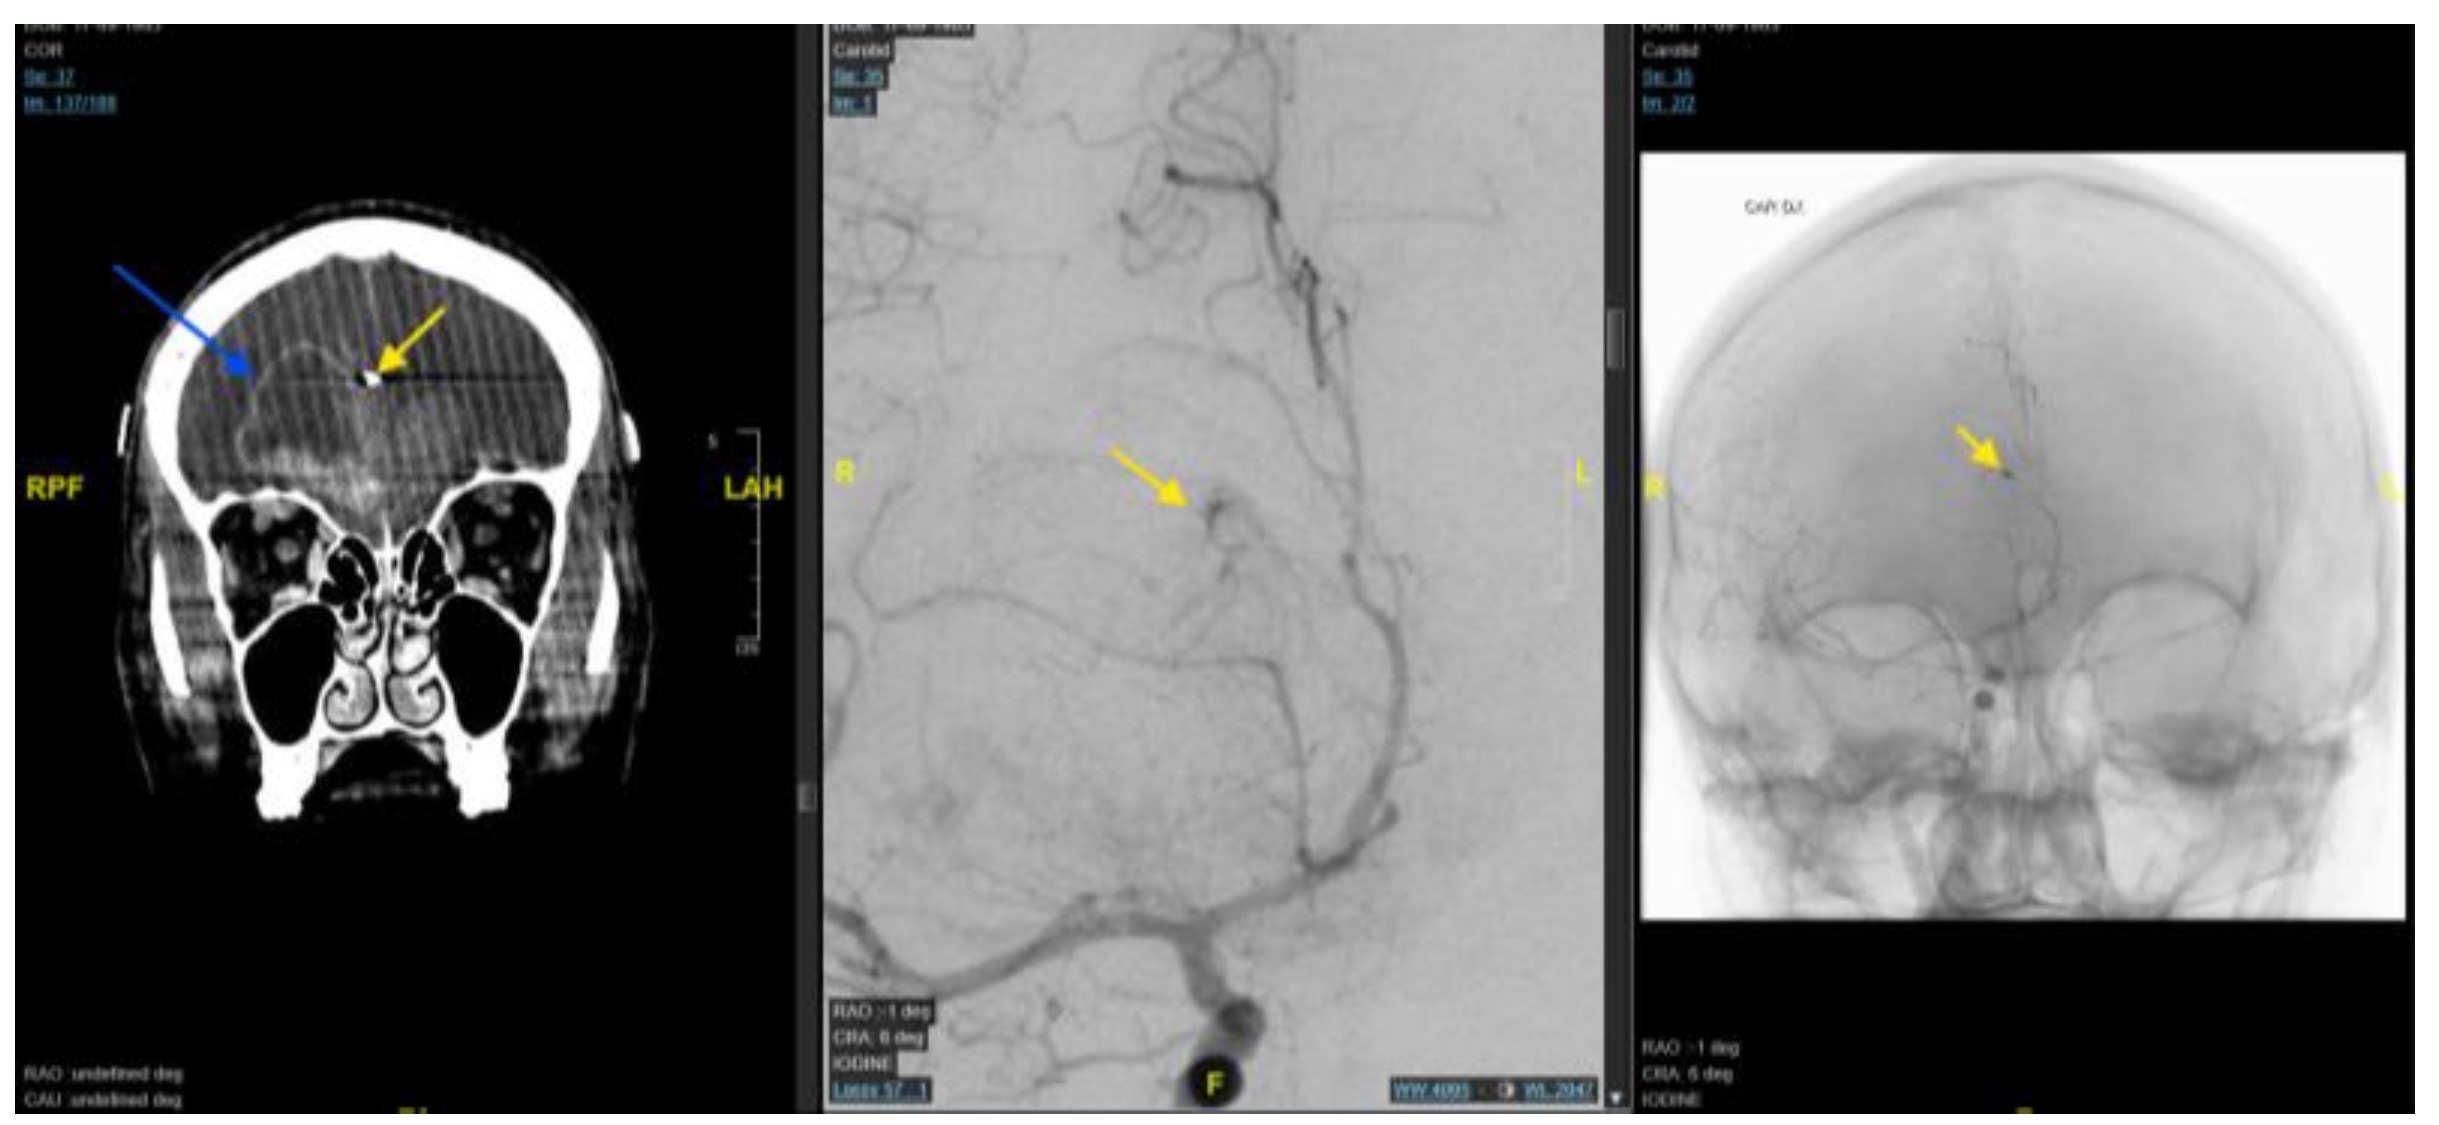

Background and Clinical Significance: Glioblastoma is the most common and aggressive primary malignant brain tumour in adults. Maximal safe surgical resection remains the cornerstone of treatment; however, tumour vascularisation may increase the risk of in-traoperative bleeding and complicate surgical management. Preoperative endovascular embolisation is commonly used for highly vascular intracranial tumours such as men-ingiomas, whereas its role in glioblastoma remains poorly defined. A focused literature review using the search string (((preoperative) AND (endovascular)) AND (embolization)) AND (glioblastoma) identified only two relevant publications, highlighting the scarcity of available evidence. In this context, we report a case series of three patients with intra-cranial lesions suspected to be high-grade gliomas who underwent preoperative angi-ographic evaluation and, when feasible, endovascular embolisation prior to surgical resection. Case Presentation: Three patients presenting with large intracranial lesions suggestive of high-grade glioma underwent preoperative digital subtraction angi-ography to assess tumour vascular supply (histological analysis confirmed the diagnosis of glioblastoma). In a 61-years-old woman with a right frontal tumour, selective catheteri-sation of a frontal branch of the right anterior cerebral artery enabled embolisation with coils, achieving partial tumour devascularisation before surgery. A second patient, a 53-year-old man with a large left temporo-fronto-insular mass extending to the corpus callosum, underwent embolisation of tumour feeders arising from the anterior choroidal artery using N-butyl cyanoacrylate and Lipiodol prior to resection. In a third case, a 77-year-old man with a left temporo-parietal lesion underwent preoperative angiography that demonstrated tumour capillary blush but no catheterisable feeding arteries, and embolisation was therefore not feasible. All patients subsequently underwent surgical resection without perioperative complications or new neurological deficits. Conclusions: Preoperative angiographic evaluation may help characterise tumour vascular supply in selected glioblastoma cases. When identifiable arterial feeders are present, endovascular embolisation may represent a feasible adjunct to facilitate surgical management. Further studies are required to better define the indications, safety profile, and potential benefits of this approach.